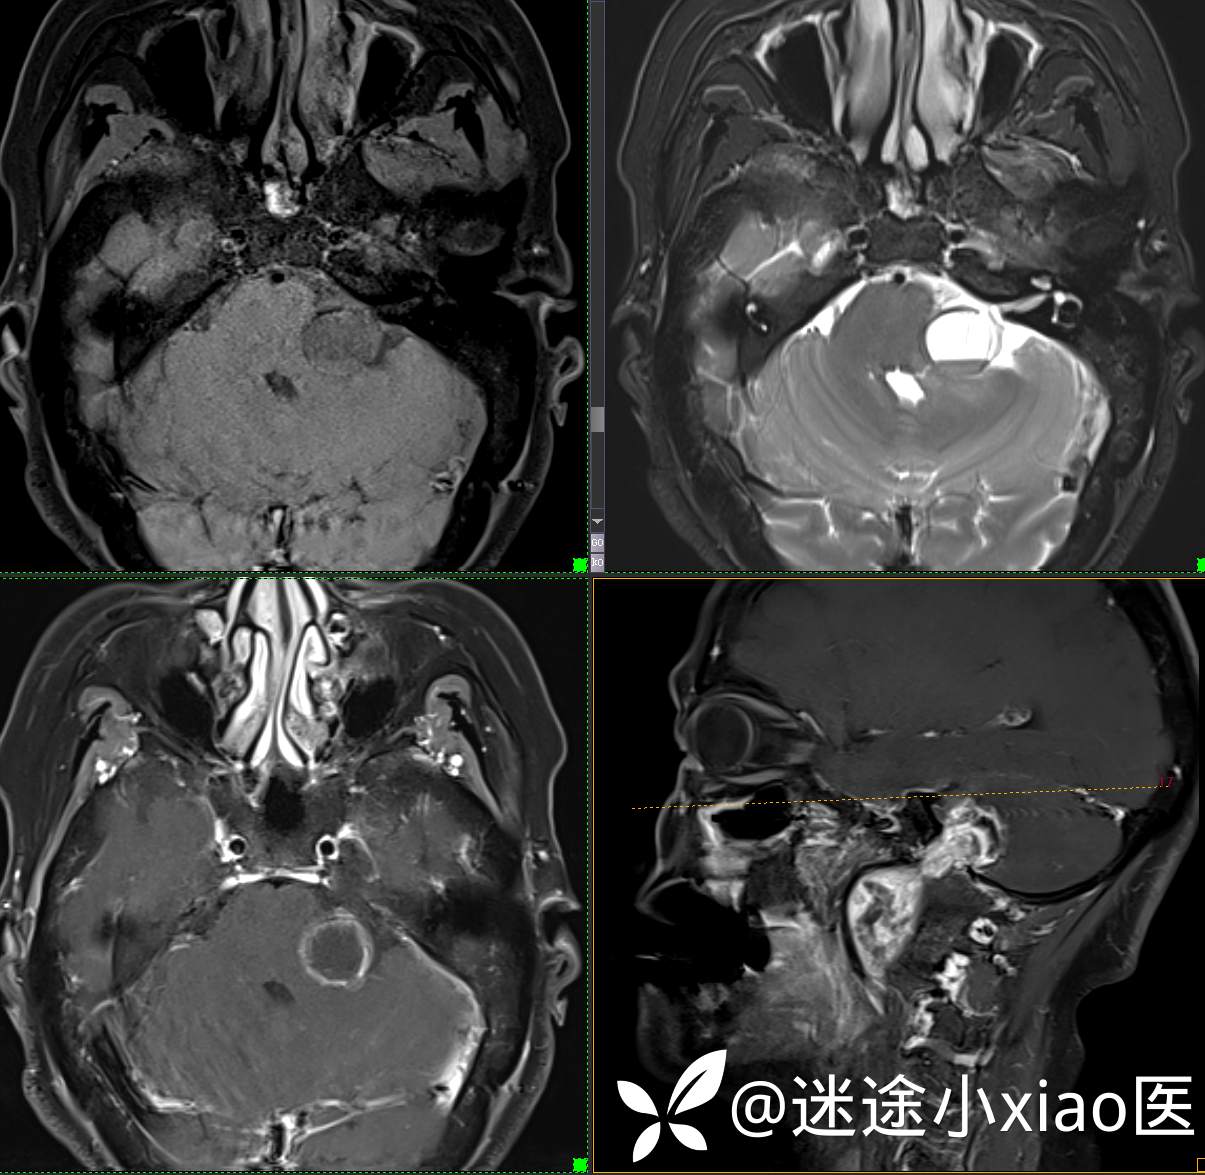

头颈组17:颈静脉孔区占位,副神经节瘤?神经鞘瘤?脑膜瘤?

患者性别:女

患者年龄:57岁

主 诉:  声音嘶哑进食困难伴左侧颌部麻木半年

现病史:  【患者半年前无明显诱因出现声音嘶哑,进食困难,只能进食糊状食物,伴有恶心呕吐,无明显头痛头晕,未加重视。

神经鞘瘤 (117)